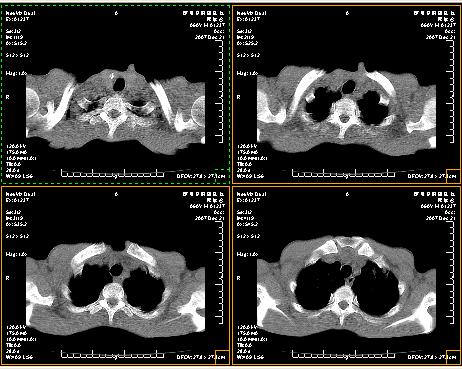

两肺示有散在大小不等类园形边缘不整密增高影.

考虑多发性转移瘤.请各位老师指导.

两肺及胸膜多发性转移瘤。纵隔淋巴结转移.

双侧胸壁见多发结节软组织密度灶,两肺内见广泛结节状、面团样影,两肺及胸膜多发性转移瘤。支持

根据:病变确实是多发,但大部分边缘不光滑,欠规整,密度不均匀。也就是说“大部分病灶不是典型转移瘤的表现”。转移瘤可以不典型,但如此大部分不典型,却是很少见的。结合发烧病史,考虑肺多发小脓肿或其他炎性病变,如霉菌等感染!建议痰培养,抗炎治疗后复查!